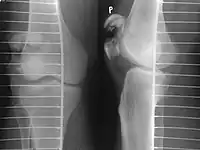

Comminuted fracture of patella